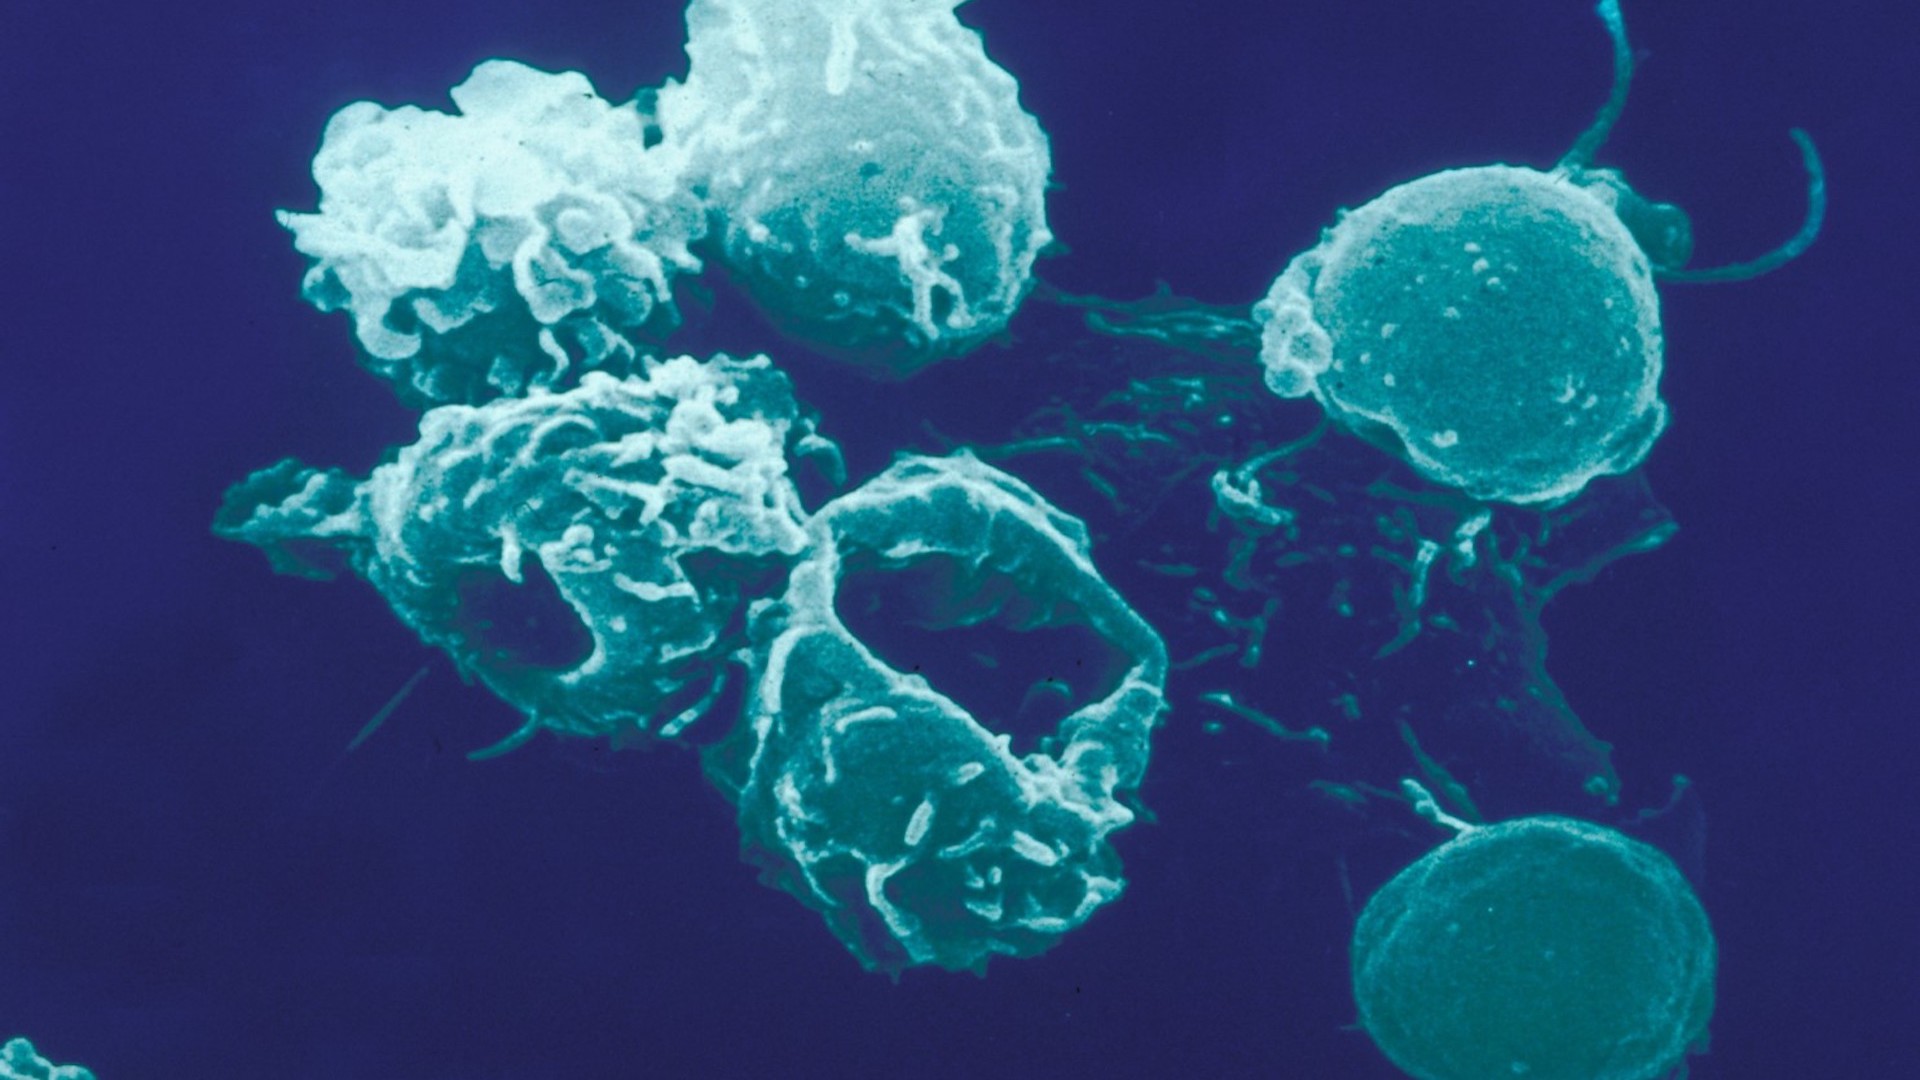

Lymphopoïèse